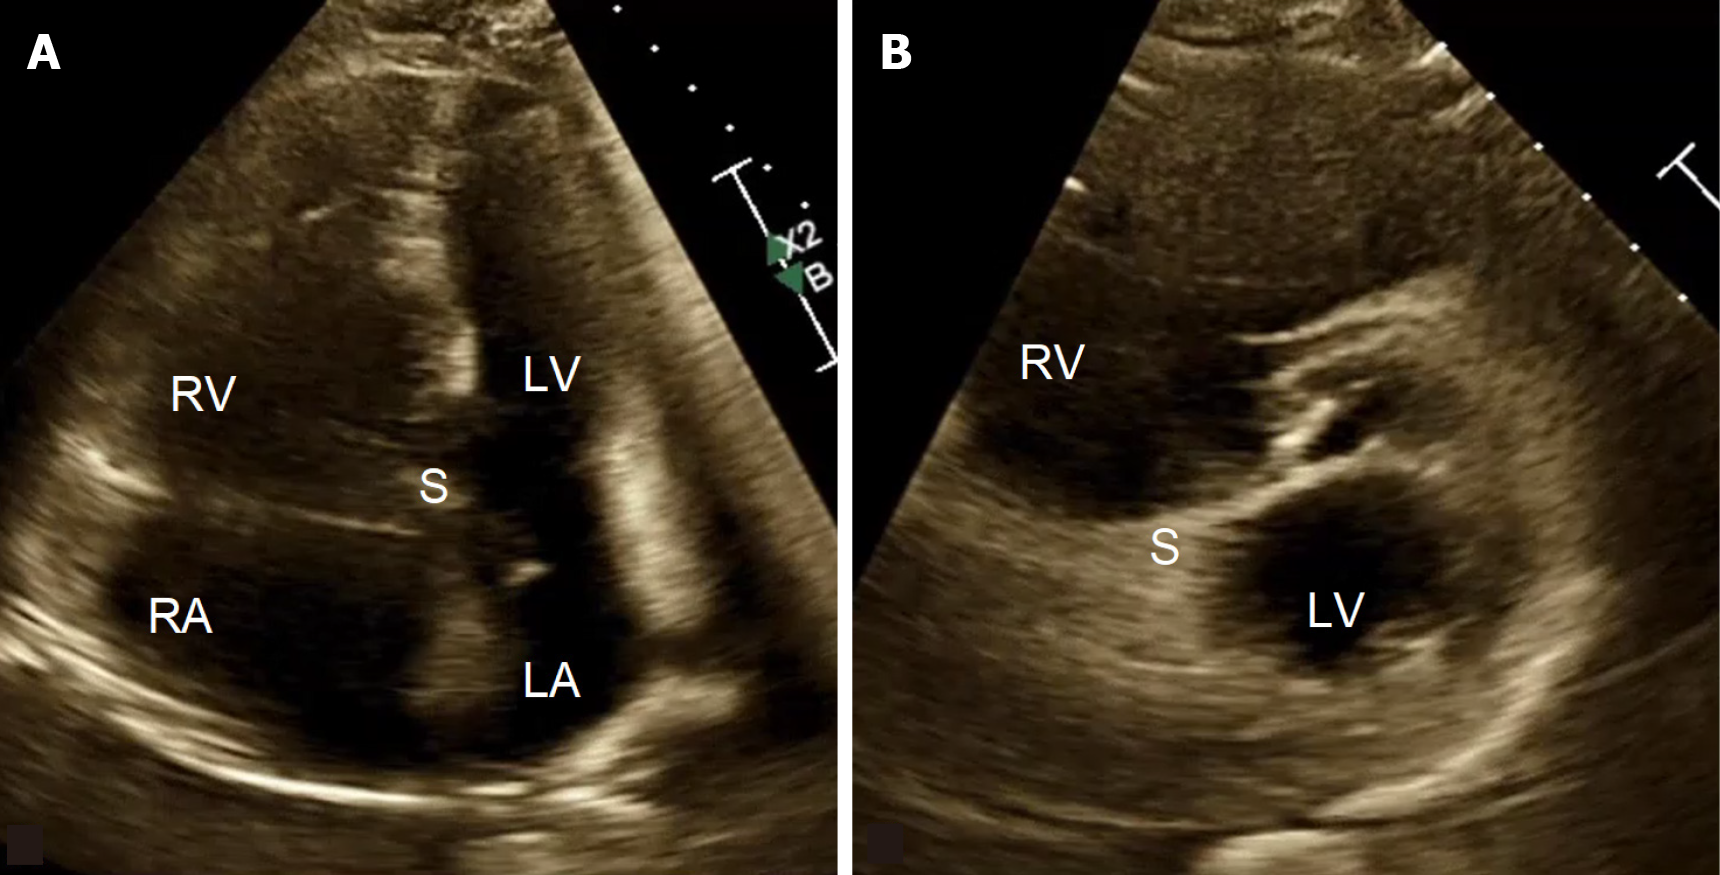

Figure 1 Echocardiographic appearance of right ventricle failure showing RV dilation and compression of the left ventricle, septal flattening, and D-shaping of left ventricle.

A: Apical 4-chamber view; B: Parasternal short-axis view. RV: Right ventricle; LV: Left ventricle; RA: Right atrium; LA: Left atrium; S: Interventricular septum.